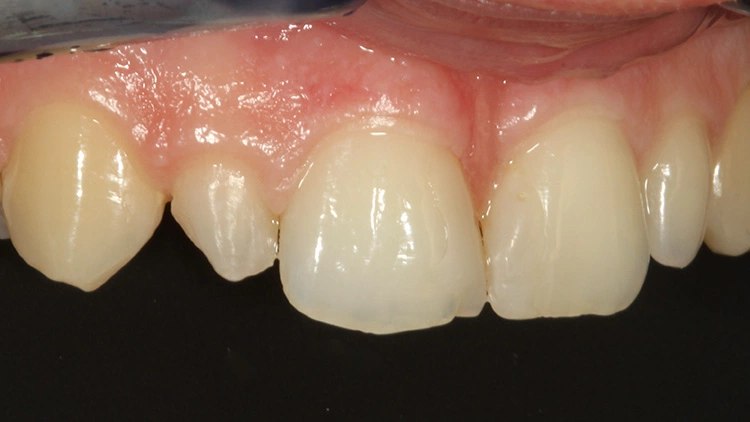

Die finale Ausarbeitung und Politur erfolgten mit Komposit-Hartmetall-Finierer (H48 LQ, Komet, Lemgo), flexiblen Scheiben (Soflex Pop-On XT 2381 M, F und SF, 3M, MN, USA) und speziellen Komposit-Polierern (Optra-Gloss, Ivoclar, Vivadent). Die Abbildung 11 zeigt die Restauration unmittelbar nach Ausarbeitung und Politur, die Abbildung 12 bei einer Nachkontrolle nach 1 Jahr. Prof. Dr. Ernst

Prof. Dr. Ernst Prof. Dr. Ernst